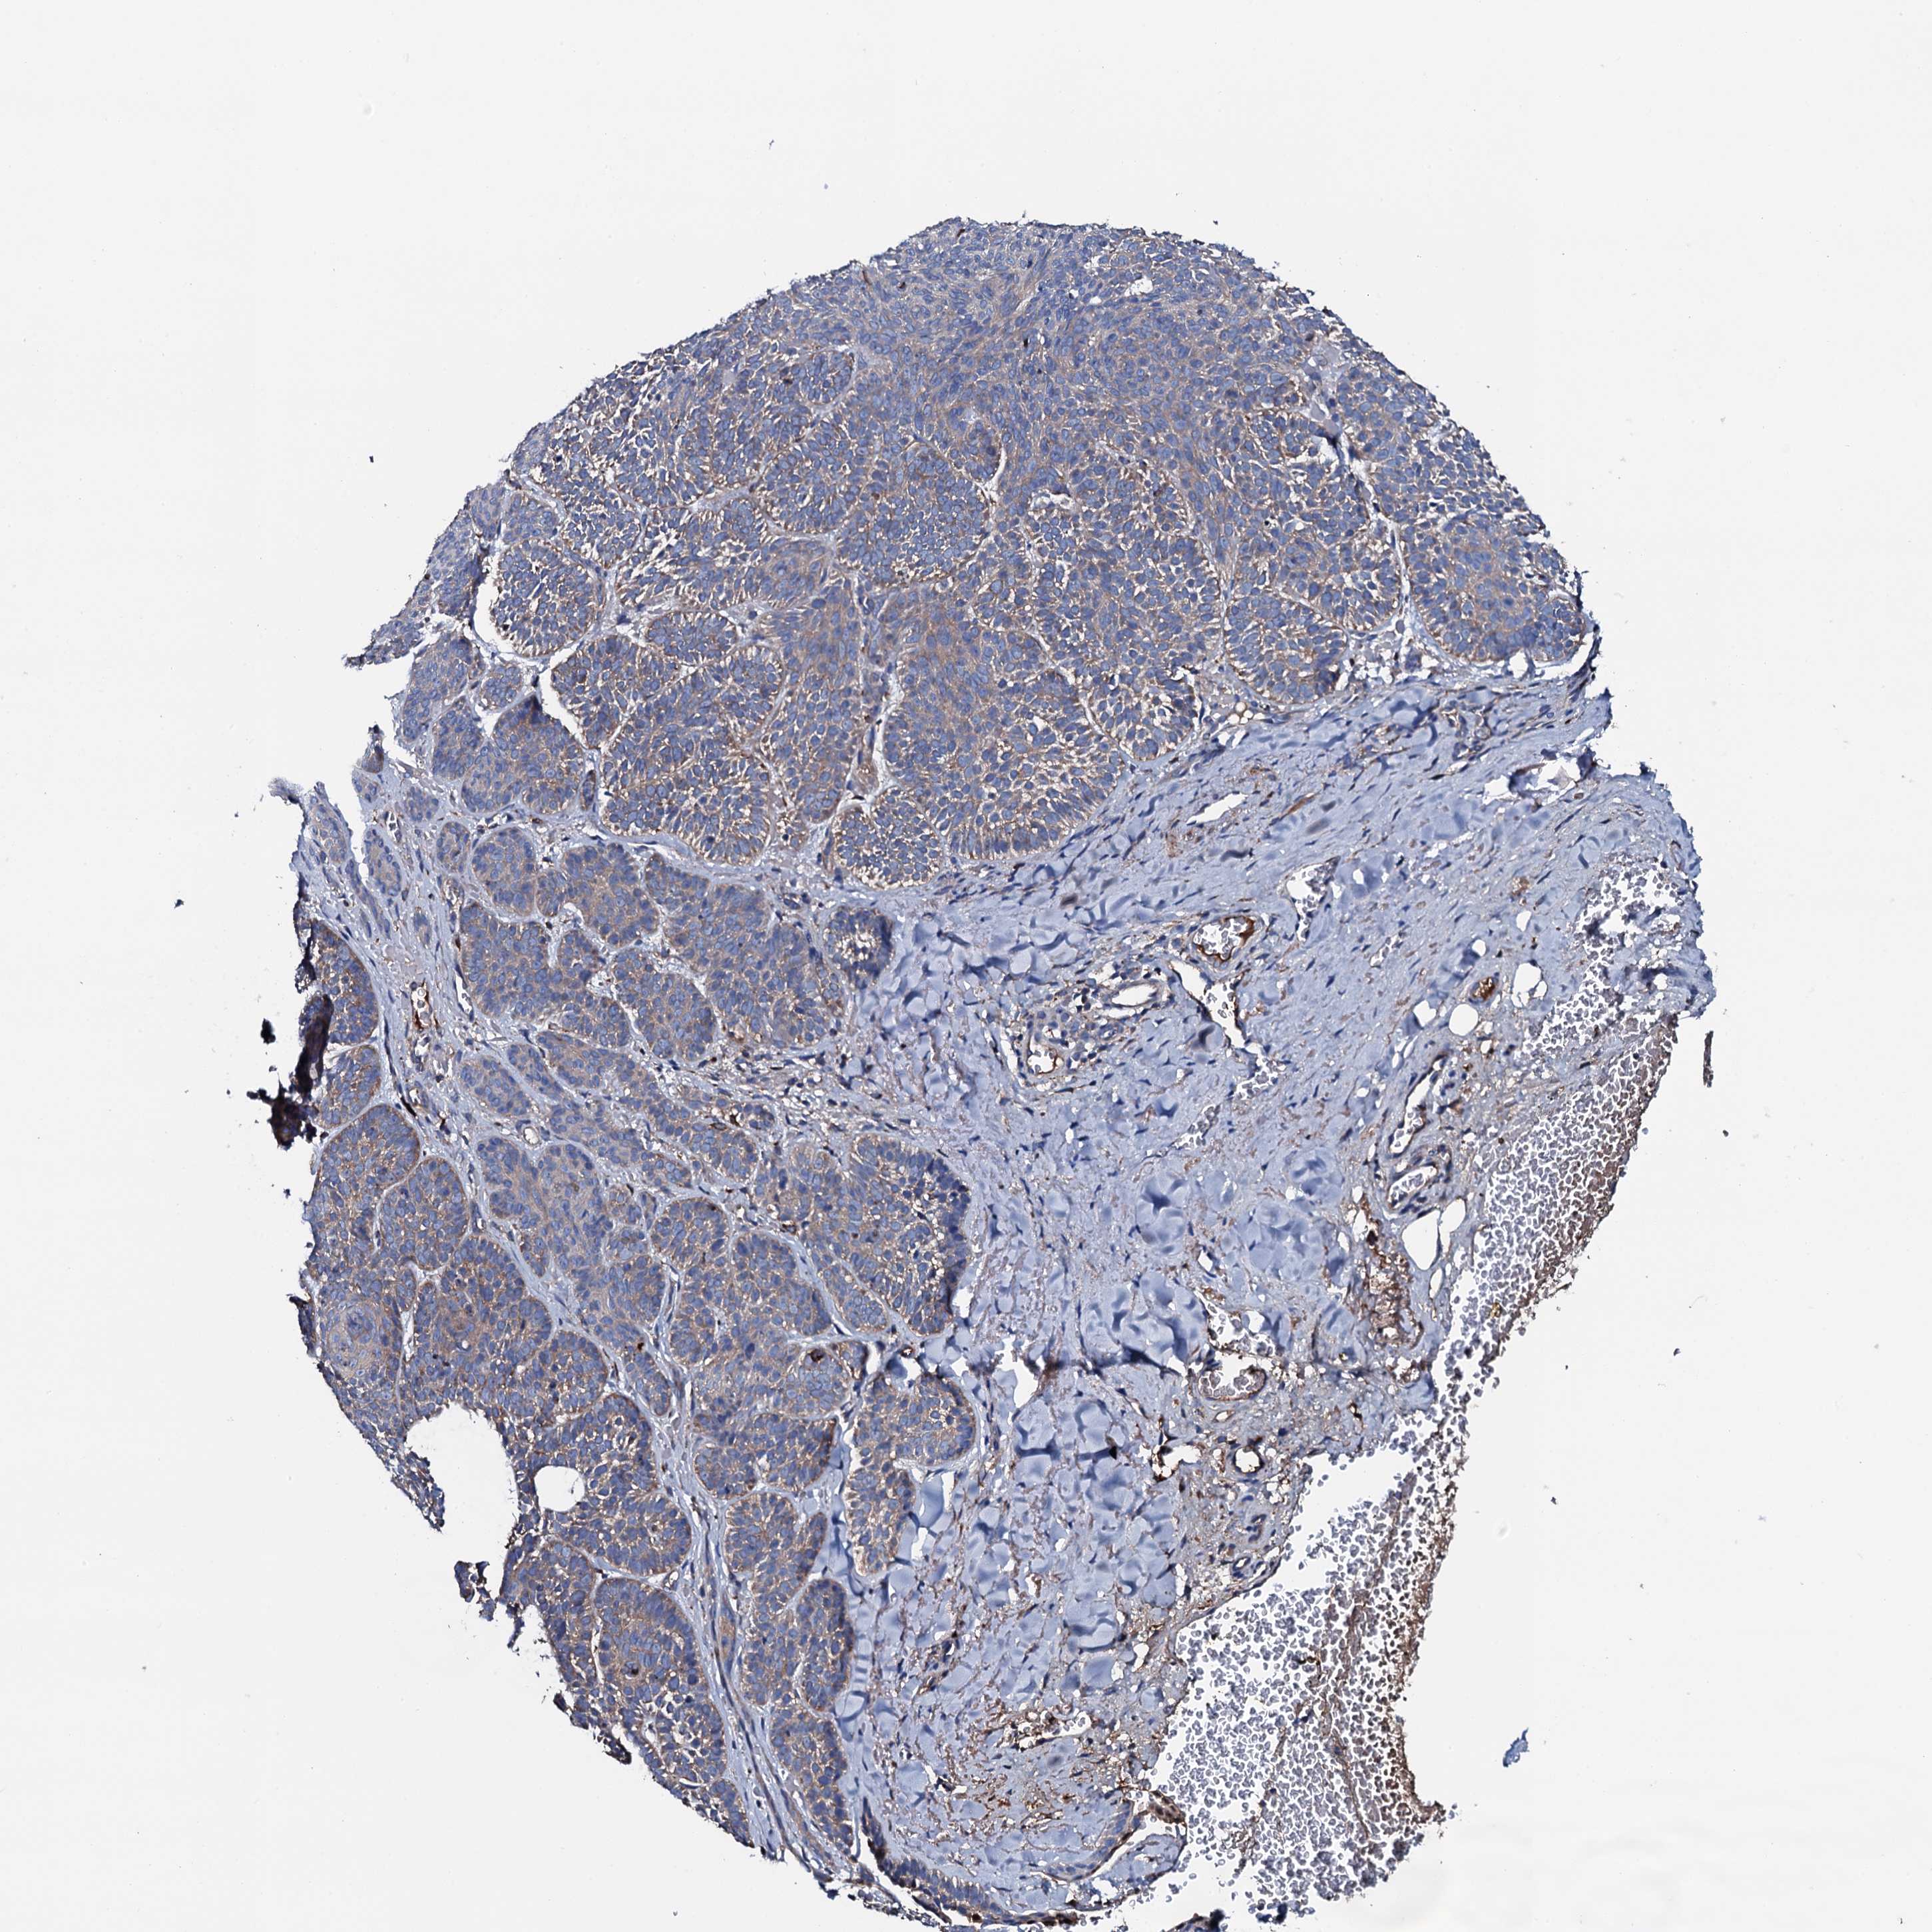

CANCER SKIN CANCER Show tissue menu

Basal cell and squamous cell cancer

SKIN CANCER - Protein expressioni

A mouse-over function shows sample information and annotation data. Click on an image to view it in a full screen mode. Samples can be filtered based on level of antibody staining by selecting one or several of the following categories: high, medium, low and not detected. The assay and annotation is described here.

Each image is clickable and will lead to virtual microscopy that enables deeper exploration of all samples and also displays staining intensity scores, fraction scores and subcellular localization as well as patient and tissue information for each sample.

Antibody HPA020873

Antibody HPA040413

Basal cell carcinoma

Squamous cell carcinoma, NOS

Squamous cell carcinoma, metastatic, NOS